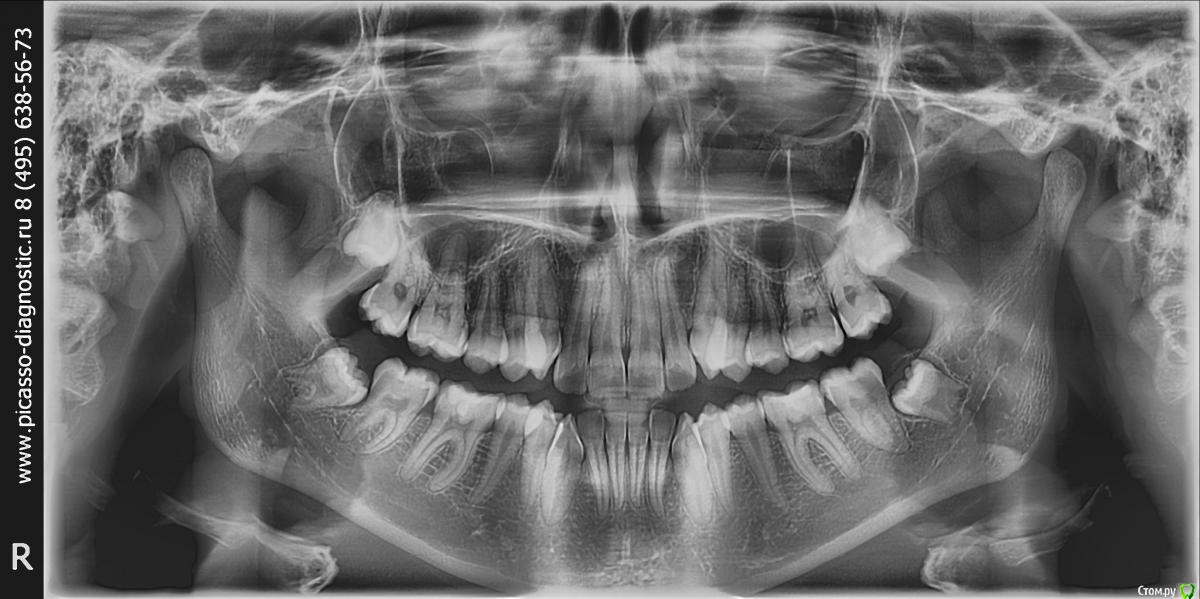

Orange1 Опубликовано 17 марта, 2017 Поделиться Опубликовано 17 марта, 2017 (изменено) Коллеги а в этом случае как думаете по верхним 8 кам? Изменено 17 марта, 2017 пользователем Orange1 Ссылка на комментарий

Orange1 Опубликовано 18 марта, 2017 Поделиться Опубликовано 18 марта, 2017 Опять задачки от ортодонтов? да.настаивают на удалении верхних.без аргументов.смысл не понятен мне Ссылка на комментарий